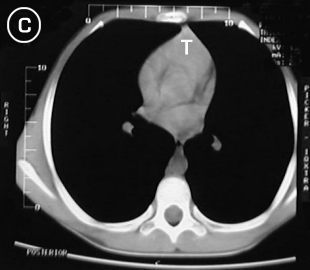

Tomografía torácica

Tomografia A Tomografia B

Estudio tomografico milimetrico, progresivo desde el vértice hasta bases pulmonares, en donde no se apreciaron procesos pleuro-parenquimatosos; Mediastino sin adenopatías; En los cortes pretraqueales (A) y (B) se aprecia imagen de densidad de partes blandas en correlacion con probable timo hiperplasico y/o timoma, extendiendose distalmente anterior a los grandes vasos (C), observese su ausencia en el corte precordial inferior (D), donde apreciamos una silueta cardiaca de morfologia conservada, las bases pulmonares y el hemi-abdomen superior no mostraron alteraciones.

Tomografia C Tomografia D